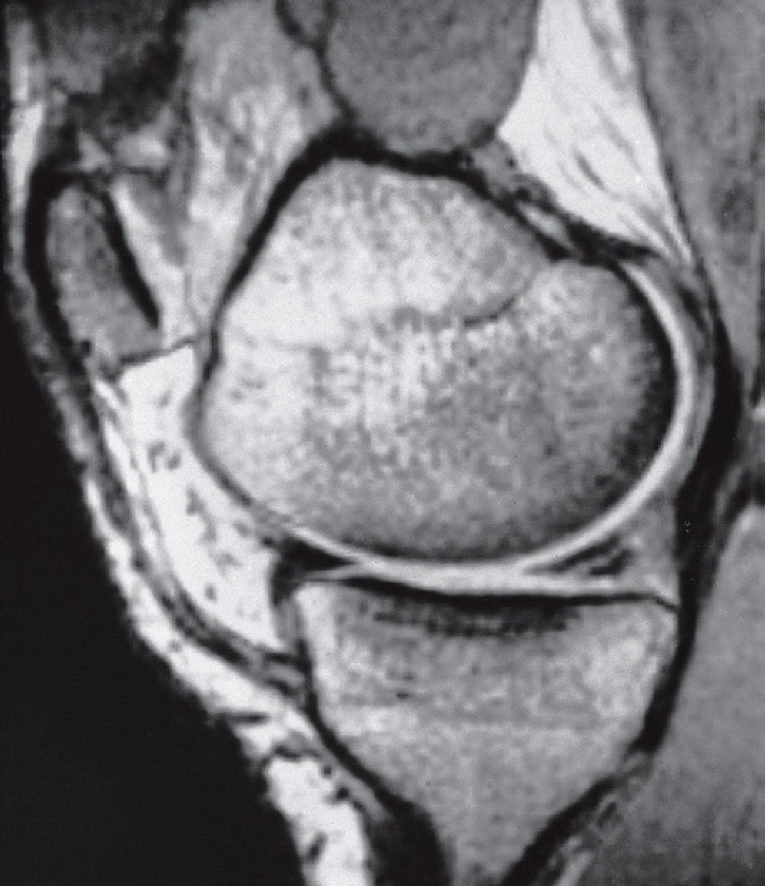

Tear of the medial meniscus. Sagittal MRI through the medial part of the knee joint showing a tear in the posterior horn of the medial meniscus. The anterior horn appears normal.